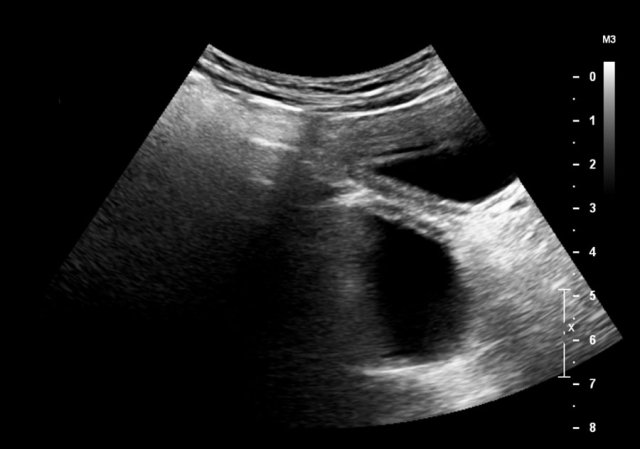

Here an antenatally detected cyst, confirmed after birth in a newborn girl.

A cyst with a fluid-fluid level is seen.

At operation a torsion of the left ovary was found.